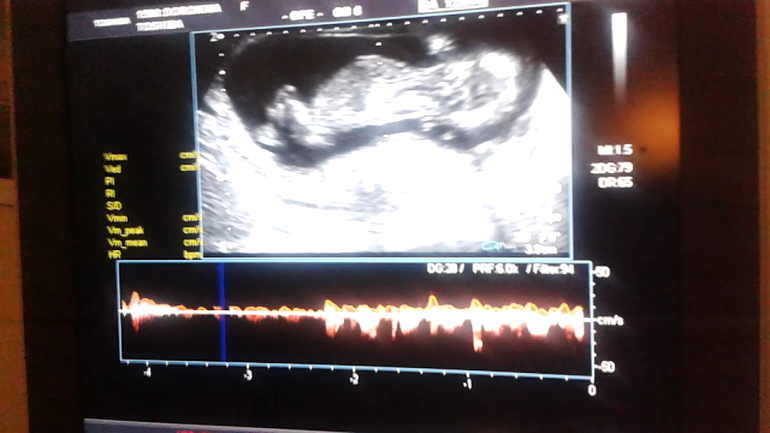

Нужно мнение зала:) пол по узи в 13 недель.

УЗИ, КТГ, доплерУзист сказал.что не видно. Хотя отчетливо мелькает какой-то "шарик". Пытала врача,мальчик ли. Она молчит. Зато подруга уверена.что да😃 а вы как думаете? Разве такое бывает у девочек?

Фото между ножек снизу.

На таком сроке можно только по наклону полового бугорка посмотреть, а это в другом ракурсе делают- строго в профиль, когда всего ребеночка видно с головы до попки, а снизу и у мальчиков, и у девочек будет виден этот бугорок.

На 13 неделях снизу пол ещё не смотрят только по наклону бугорка потому что он и у девочек и у мальчиков есть, только под разным углом

Там у обоих полов точит на таком сроке! Потом у девочек исчезает! Он либо вверх направлен либо вниз. От этого зависит мальчик или девочка)